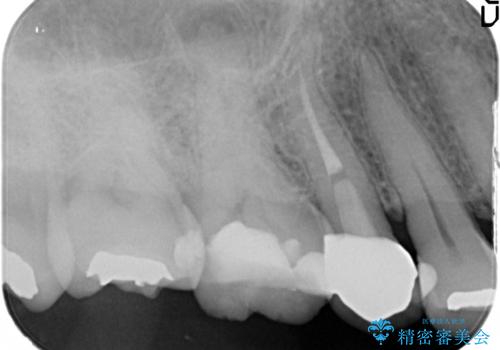

- 定期検診にて、奥歯の頬側歯肉にサイナストラクトが発見された患者様です。

根管治療から歯冠修復まで行っております。

サイナストラクト(瘻孔)から原因歯を特定し治療を行っております。根管治療を行った歯牙は破折リスクが高くなるため被せものによる治療を提案しております。